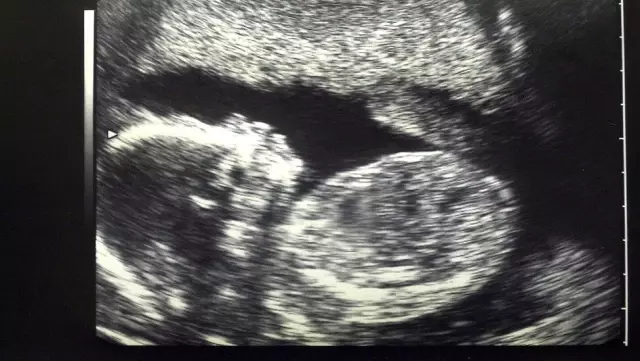

Belçika‘da hamlie bayanlarla yapılan bir araştırmada plasentalarda (döleşi) hava kirliliği partikülleri bulundu.

Araştırma anne karnındaki bebeklerin de direkt trafik ve fosil yakıtların yakılmasından kaynaklanan kirliliğe maruz kaldıklarına işaret ediyor.

Anne ve fetüsün sirkülasyon sistemlerini birbirinden ayıran bir organ olan plasenta, dokuların oluşması için gerekli olan besinleri ve oksijeni bebeğe taşıyor, ayırdığı atık hususları annenin bedenine gönderiyor.

Araştırma, annenin soluduğu havadaki partiküllerin plasenta bariyerine sızabildiğini gösteren birinci çalışma olması açısından kıymet taşıyor.

İncelenen tüm plasentaların cenin tarafında, her bir milimetreküpte binlerce partikül bulundu.

Kirli havaya maruz kalmanın düşük, prematüre doğum ve bebeklerin zayıf doğmasına yol açabildiği biliniyor. Araştırma bunların yalnızca kirliliğin annelerde yol açtığı inflamatuar karşılıktan değil, şahsen parçacıklardan kaynaklanabileceğine işaret ediyor.